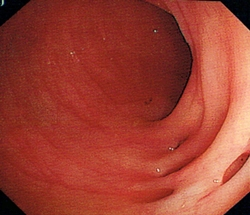

大腸癌是本港第3常見的癌症,亦是本港致命癌症中的第2位。大腸癌篩查可及早識別未出現病徵的大腸癌患者或高危人士,讓其及早接受治療,大大提高治癒率,而在大腸鏡檢查過程中切除大腸腺瘤,則可避免腺瘤演變成癌症。經計劃確診大腸癌的個案中,約2400宗已進行初步分析,結果顯示約56%屬於早期個案,治癒率較高。